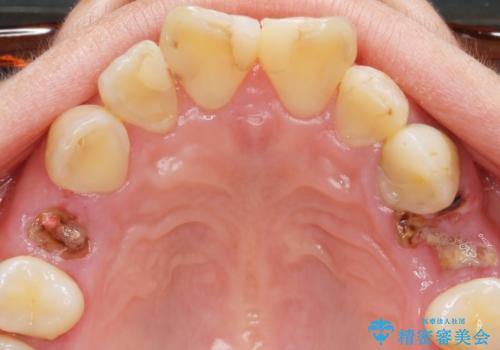

前歯の虫歯 つぎはぎの歯をセラミックに

- 矯正治療後に、前歯の樹脂の詰め物のやりかえを提案していましたが、治療は当時行いませんでした。

その後3年間来院がなく、その間に前歯の虫歯の進行があり、治療を行いました。

やはり、樹脂で虫食い状になってしまうと虫歯が進行しやすくなっているためクラウンがおすすめです。